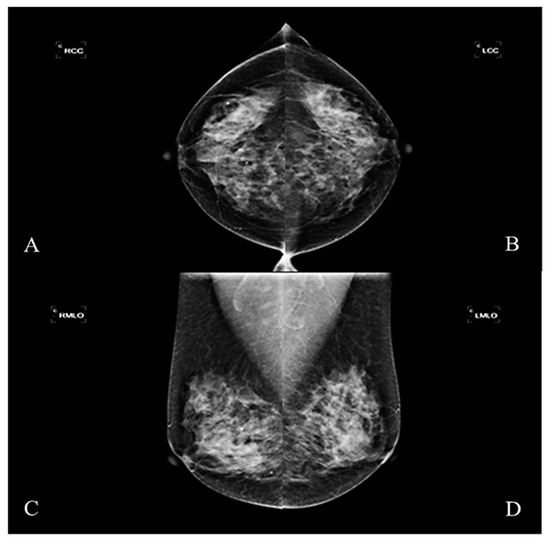

This study was designed as a retrospective group experiment and collected mammography cases and diagnostic reports from 2016–2017, which had been reviewed by the Medical Ethics Committee of E-DA Hospital (EMRP-107-031). The imaging instrument used was Hologic Lorad Selenia. Each case in the study was irradiated with four images from multiple angles. These were the right craniocaudal view (RCC), the left craniocaudal view (LCC), the right mediolateral oblique view (RMLO), and the left mediolateral oblique view (LMLO) (Figure 1). Most breast tissue can be sighted in a single image with MLO View, such as pectoralis major and axillary lymph nodes. The CC view can avoid medial tissue missed with the MLO view.

Figure 1. The mammographic image. (A) Right craniocaudal view (RCC), (B) left craniocaudal view (LCC), (C) right mediolateral oblique view (RMLO), (D) left mediolateral oblique view (LMLO).